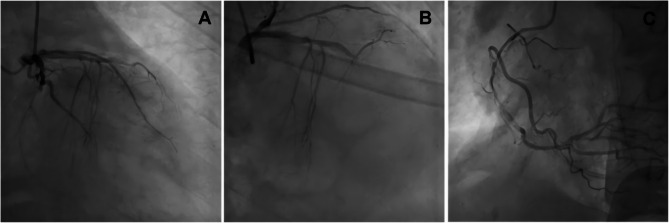

男性,64岁,表现为急性左肢体无力,脑CT灌注成像未见异常。患者很快出现心脏骤停,心肺复苏成功后冠状动脉造影显示前降支和旋支中段完全闭塞,右侧冠状动脉中段弥漫性病变。非典型AMI表现使急诊诊断复杂化,需要高度的临床警惕和在初步评估时进行广泛的鉴别评估。

A 64-year-old man presented with acute left-sided limb weakness and no abnormalities on brain CT perfusion imaging. The patient soon experienced cardiac arrest, and coronary angiography after successful cardiopulmonary resuscitation demonstrated complete occlusion of the anterior descending branch and circumflex branch mid-sections, as well as diffuse lesions in the right coronary mid-section. Atypical AMI manifestations complicate emergency diagnosis, necessitating high clinical vigilance and broad differential assessment during initial evaluation.